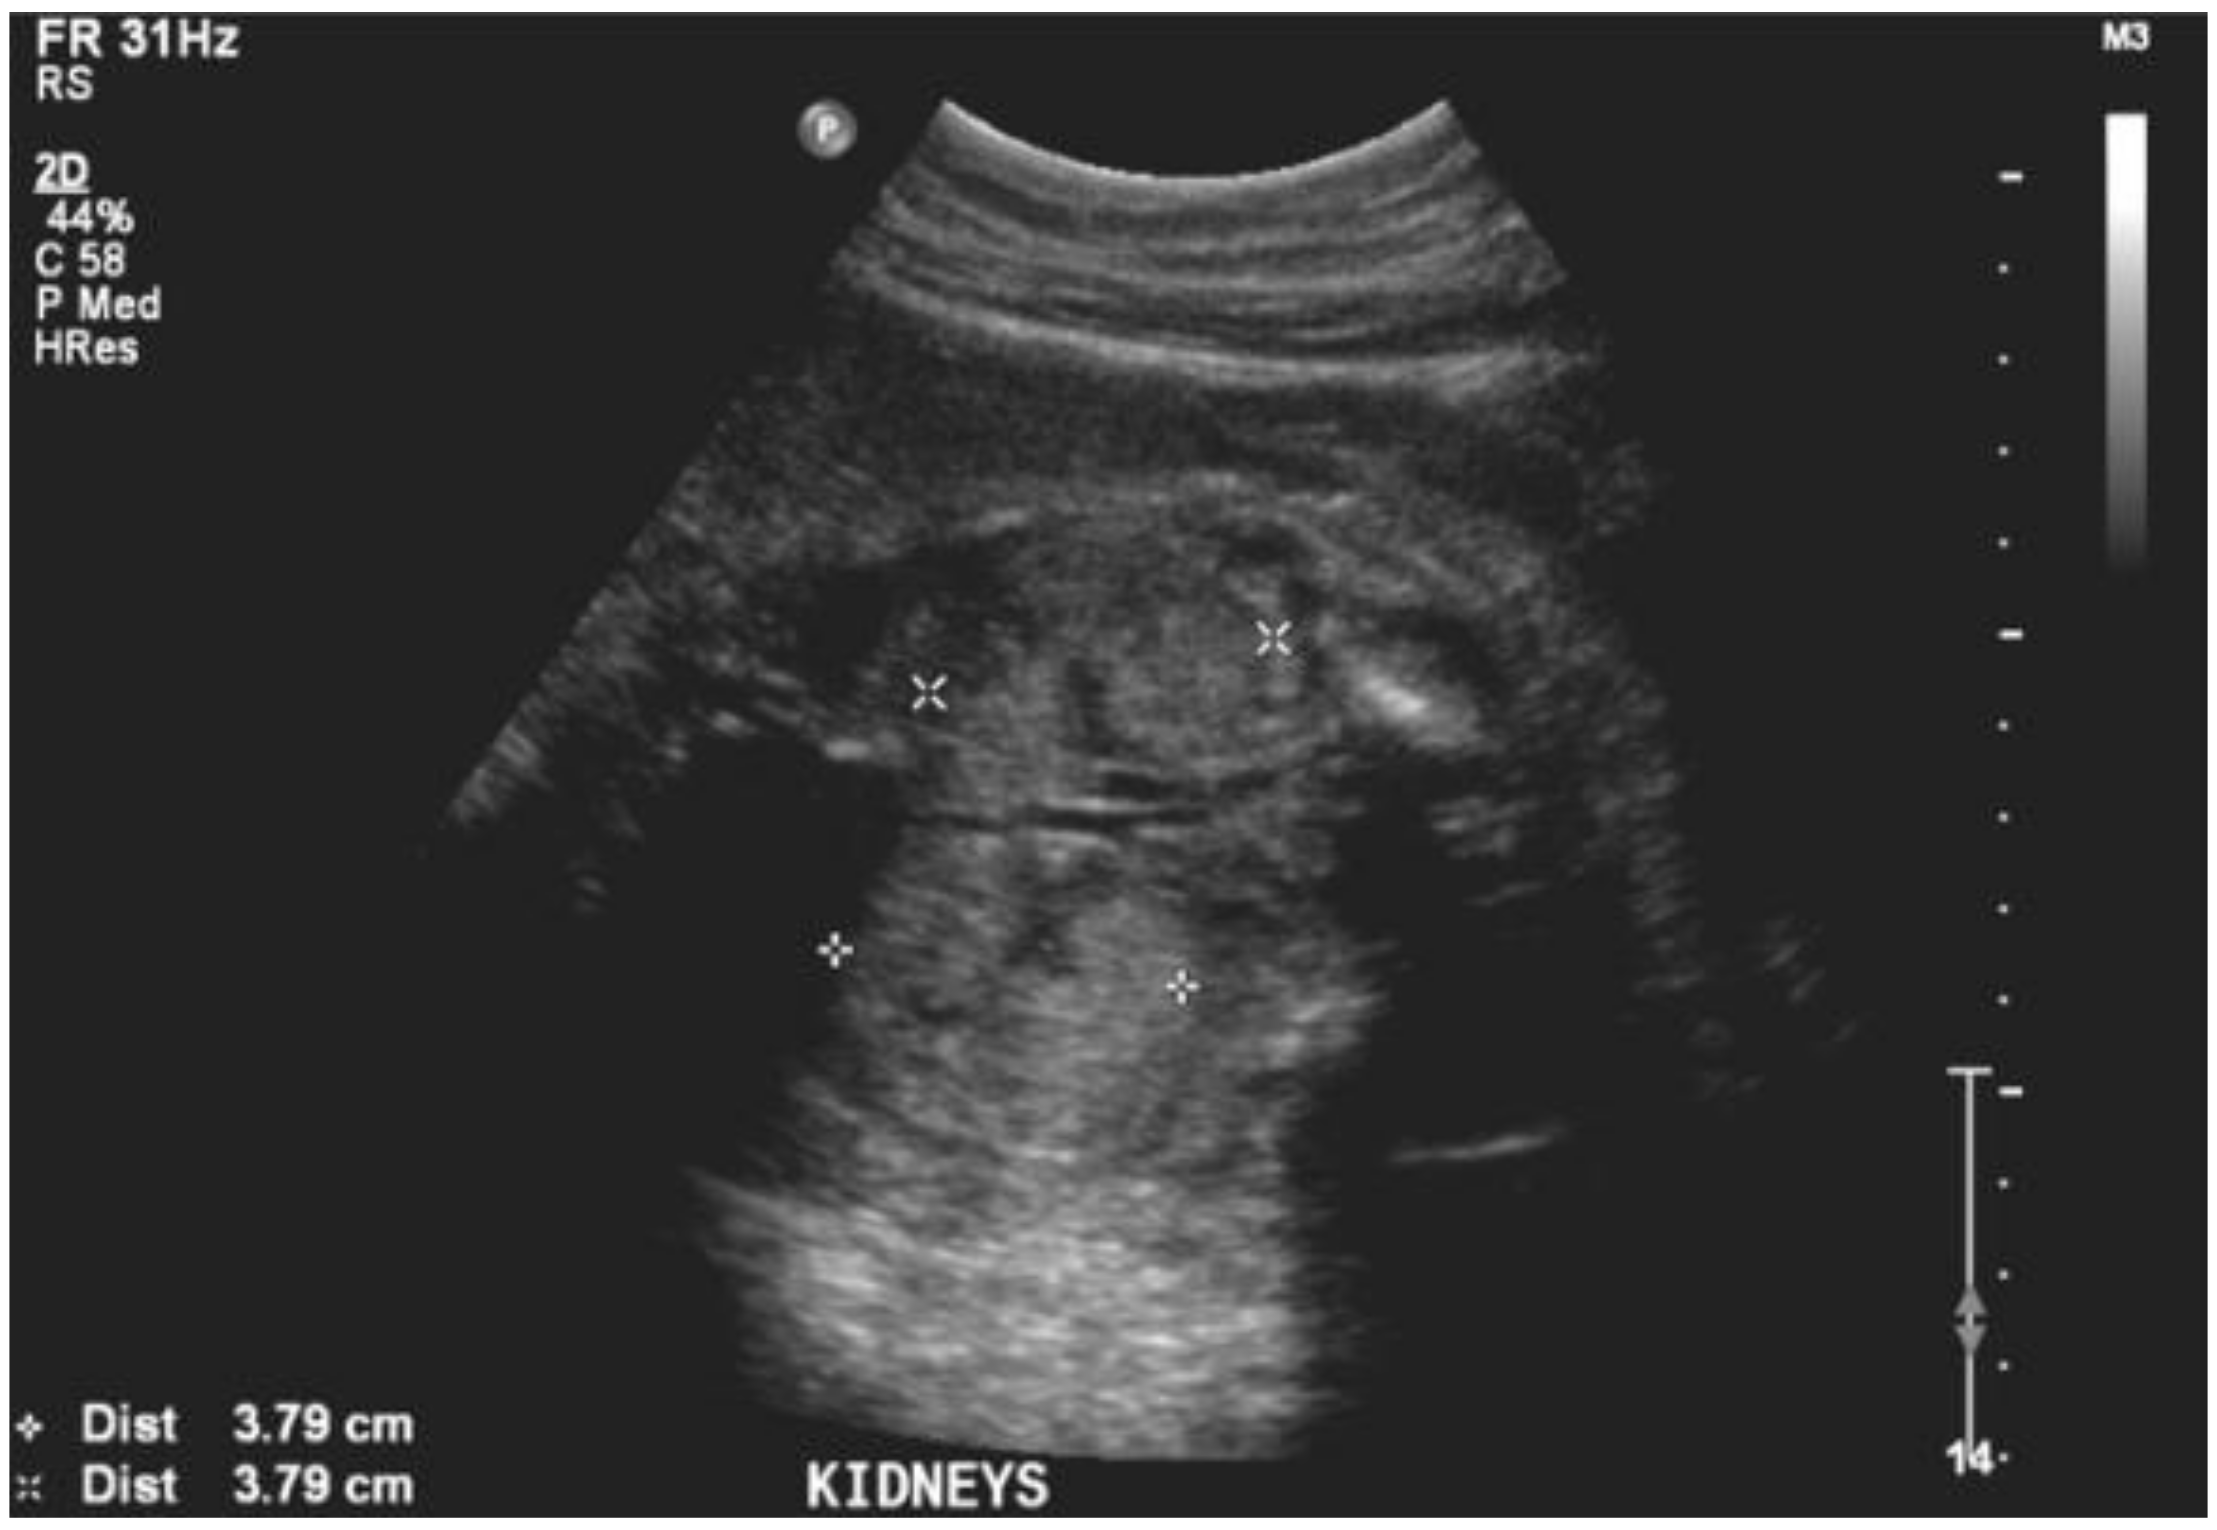

During her second trimester, the mother was noted to have progressively increasing edema, albeit with normal blood pressure. During a routine obstetrical visit at 27 weeks of gestation, she was noted to have 4+ urinary protein, and a 24 h urine collection revealed 11.58 grams of proteinuria, worsening shortly thereafter to 14.43 grams. Her creatinine at that time was 81 μmol/L. At the same visit, she had a fetal ultrasound, which revealed severe oligohydramnios with an Amniotic Fluid Index (AFI) of 1.7 cm, bilaterally enlarged echogenic kidneys (Figure 1), and an empty fetal bladder, albeit with a normal placenta and normal placental Doppler. The fetus was growing along the 50th centile. Figure 2 demonstrates the growth curves of the kidneys from 21 weeks to 27 weeks of gestation.

Figure 1. Ultrasound image of fetal kidneys at 27 weeks of gestation.